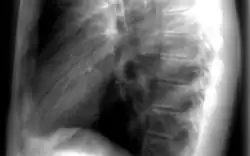

Les informations provenant des différentes structures traversées par le faisceau de rayonnements sont projetées sur un même plan pour former l'image. Par conséquent, il est souvent nécessaire de réaliser deux projections, à différentes incidences, pour pouvoir localiser une structure dans les trois dimensions de l'espace. Par exemple, en médecine, il s'agit fréquemment d'incidences de face et de profil. La loi d'atténuation des photons explique l'atténuation différentielle du faisceau à travers différentes structures, ce qui est à l'origine du contraste radiographique.

L'objet à radiographier, placé entre les positions et , à distance de la source pour que l'on puisse considérer qu'il est soumis à faisceau homogène de photons X ou gamma. Au fur et à mesure que le faisceau de photons traverse l'objet, il est atténué en fonction de l'épaisseur traversée et du coefficient d'atténuation . Ce coefficient d'atténuation dépend de l'énergie du photon et du numéro atomique Z de la structure rencontrée à la profondeur . L'organisme humain possède des tissus comme les os, très opaques aux photons, possédant donc un coefficient d'atténuation très élevé. Cela vient du fait que le tissu osseux est composé d'éléments de numéro atomique élevé comme le calcium. Le corps est aussi composé de tissus mous, peu opaques aux rayons X. Parmi eux, on différencie les organes de densité hydrique car composés essentiellement d'eau (muscles, foie) des densités graisseuses dont le coefficient d'atténuation est légèrement plus faible. Enfin, le poumon étant essentiellement composé d'air, il est qualifié d'organe de densité aérique. En effet le tissu pulmonaire, comme l'air, laisse passer la quasi-totalité des rayonnements. À la sortie du patient, le faisceau de photons n'est plus homogène mais est caractéristique des tissus traversés, on parle d'image radiante . Ces photons interagissent avec le détecteur, y déposant une énergie représentative des tissus traversés. Selon le mode de fonctionnement du détecteur, cette énergie sera utilisée pour produire l'image. La forte différence de coefficient d'atténuation entre les os et les autres tissus, crée un fort contraste de l'image, ce qui fait des rayons X un excellent outil d'imagerie osseuse. Pour obtenir une image d'organes n'ayant pas une densité spécifique, il est possible d'apporter in situ un produit de contraste de forte densité. C'est le cas pour l'imagerie des vaisseaux (injection intraveineuse d'iode), pour l'imagerie du système digestif (ingestion ou injection de baryte, à base de baryum), pour l'imagerie des articulations, ou arthroscopie (injection intra-articulaire d'iode) ou encore par exemple pour l'imagerie du système de reproduction de la femme, ou hystéroscopie (injection d'iode).